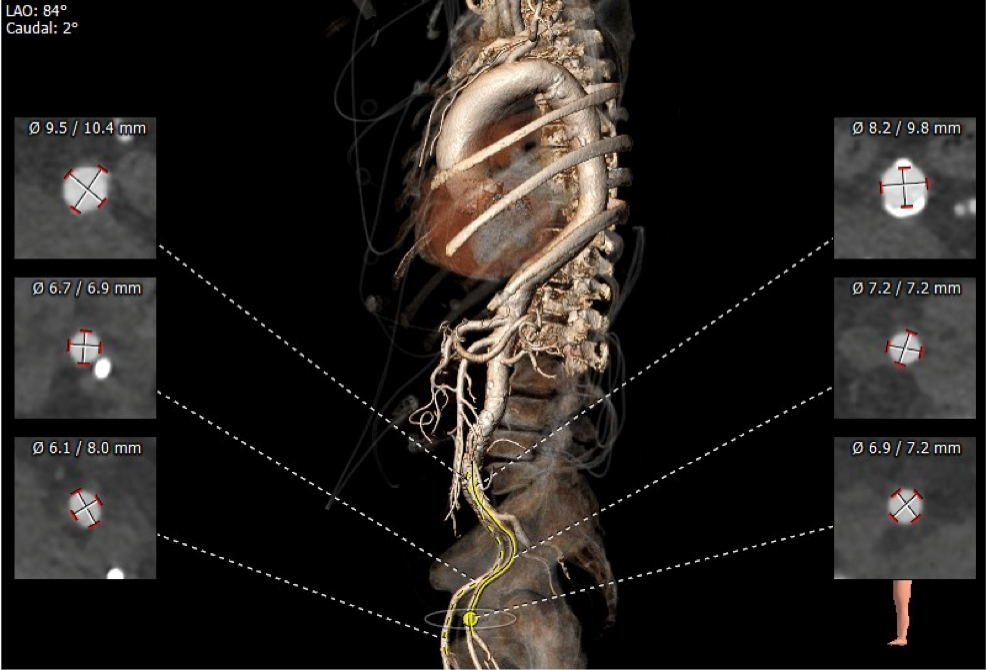

血管外周入路评估

入路血管少量钙化无其他病变,双侧血管内径良好,整体入路血管条件良好。